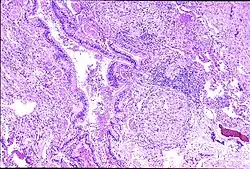

| Peribronchal non-necrotizing granuloma from berylliosis | |

Granuloma formation is seen in other diseases such as tuberculosis and sarcoidosis. Sarcoidosis, like berylliosis, also produces granulomas without a necrotic core, and so distinction between the two processes can be difficult.